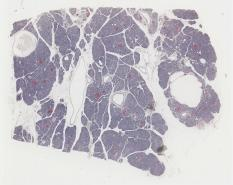

Hyperactive thyroid follicular cells [DigitalScope]

This specimen shows how hyperactive follicles would appear.

One possible cause of hyperactive follicles could be Graves disease in which autoantibodies bind to the TSH receptor on thyroid follicular cells and stimulate them to take up colloid and release active thyroid hormone. Alternatively, there could be a pituitary tumor that secretes high levels of TSH that activates the thyroid gland.

Hyperactive thyroid cells:

However, the source of the pathology in this specimen is that the animals have been treated with thiouracil, which blocks the oxidation of iodide, the result of which is that functional thyroid hormones can no longer be produced. The lack of thyroid hormones in the blood stream leads to stimulation of the pituitary to produce large quantities of TSH, causing the thyroid follicular cells to hypertrophy and resorb colloid very actively from the lumen, reducing its size. The frantic effort of these cells is futile, however, since the oxidized iodine necessary to make functional thyroid hormones is unavailable.

As such, the actual follicular cells are "hyperactive" in terms of actively taking up and processing thyroglobulin, but the thyroid status of this subject would be hypothyroid (i.e. low thyroid hormone levels). For this reason, it is essential to have lab values regarding actual thyroid function to go along with the microscopic analysis of thyroid tissue when working up patients with thyroid conditions.